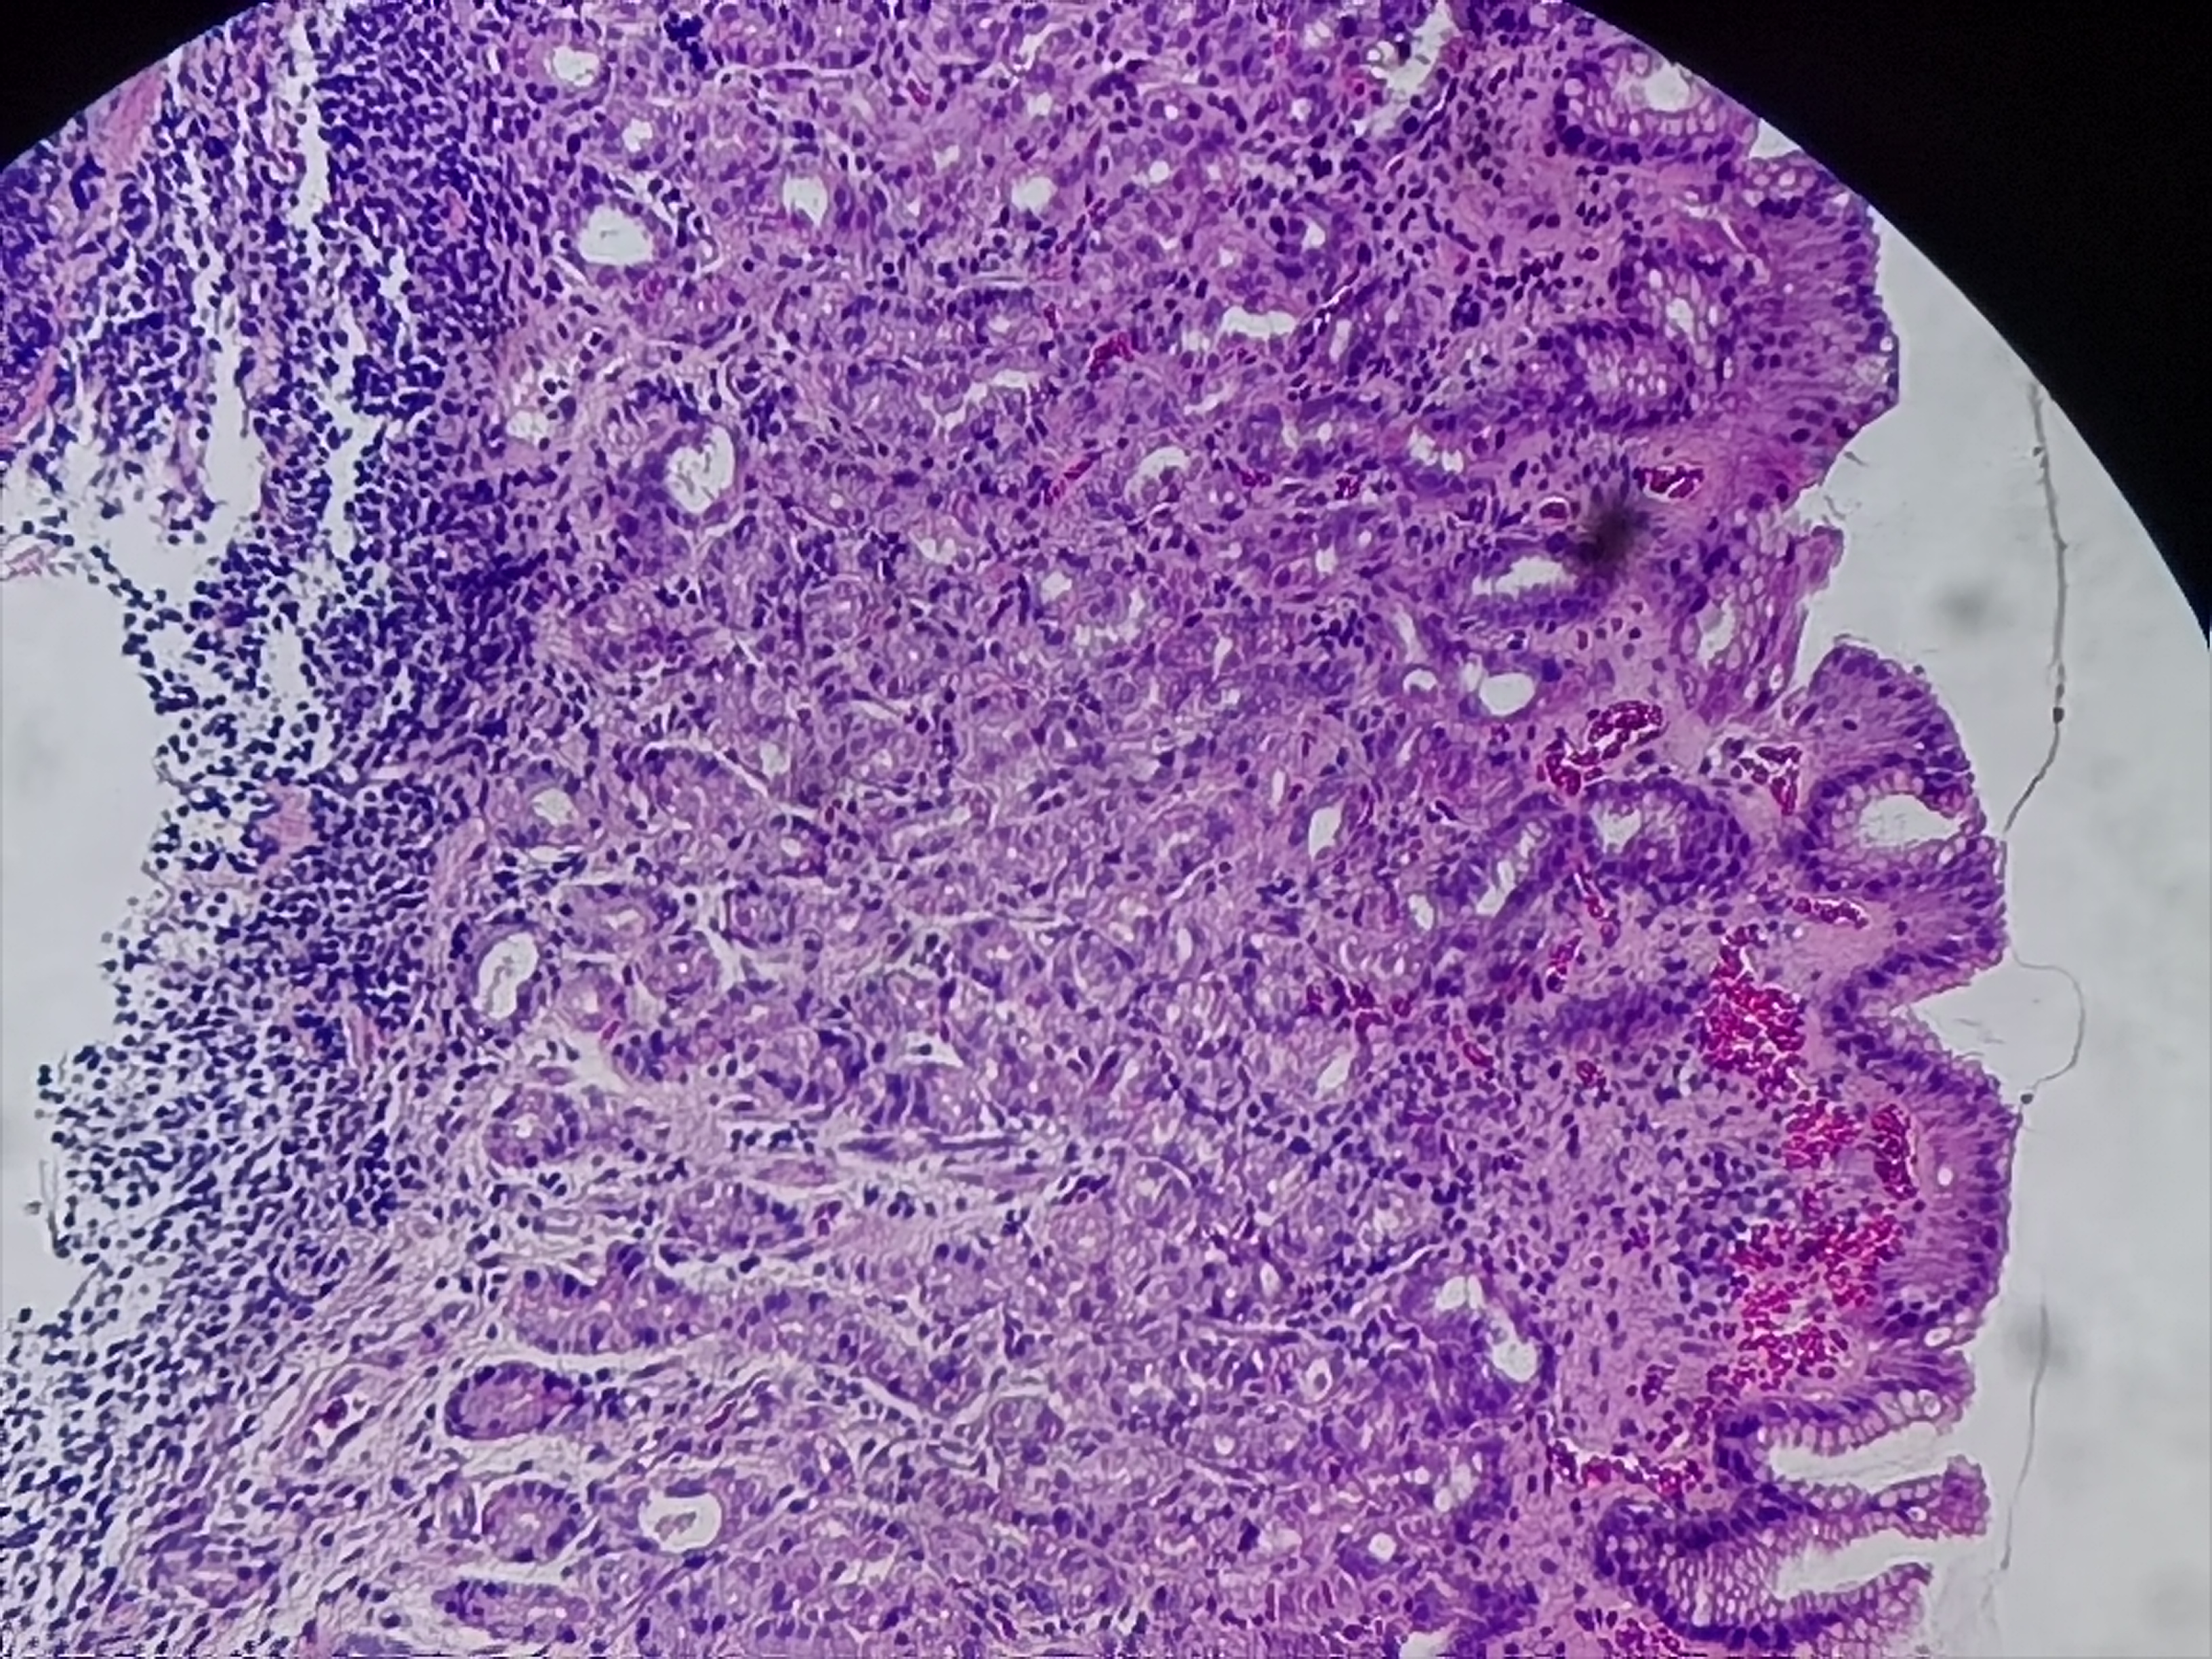

胃体活检

性别

女

年龄

60岁

胃体小弯侧粘膜粗糙

胃体粘膜活检

灰白色组织1块

慢性炎